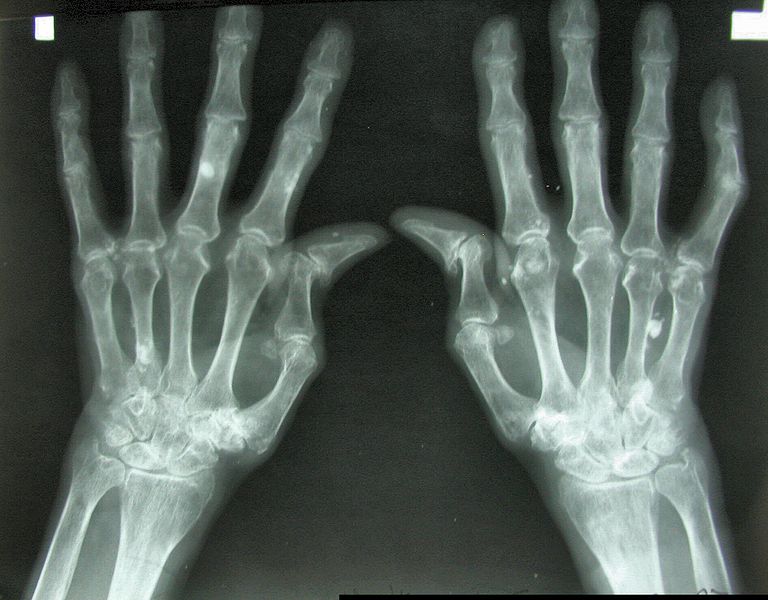

Reumatoidalne zapalenie stawów (w skrócie: RZS, dawna nazwa: gościec przewlekle postępujący, łac. polyarthritis reumatoidea, ang. rheumatoid arthritis w skrócie RA) – choroba reumatyczna o charakterze zapalnym i podłożu autoimmunologicznym. Charakteryzuje się nieswoistym zapaleniem stawów, zmianami pozastawowymi i powikłaniami układowymi. Przebiega z okresami remisji i zaostrzeń.